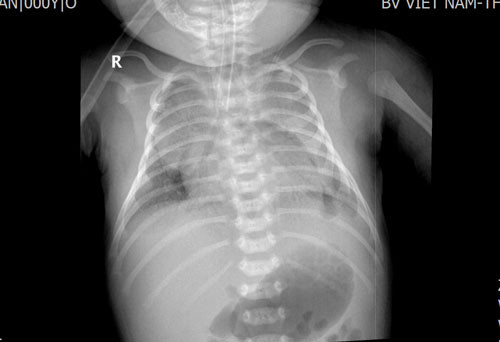

Hình ảnh chụp X-quang mờ đều 2 phổi. Nhận định tình trạng sức khoẻ trẻ có dấu hiệu nguy kịch, các bác sĩ đã chuyển phác đồ điều trị thở máy cao tần cho trẻ, dùng thuốc giãn mạch phổi, vận mạch, bơm surfactant…

Trẻ được chụp X-quang vào ngày điều trị thứ 2 cho thấy phổi mờ đều 2 bên |

Trẻ được chụp X-quang vào ngày điều trị thứ 2 cho thấy phổi mờ đều 2 bên